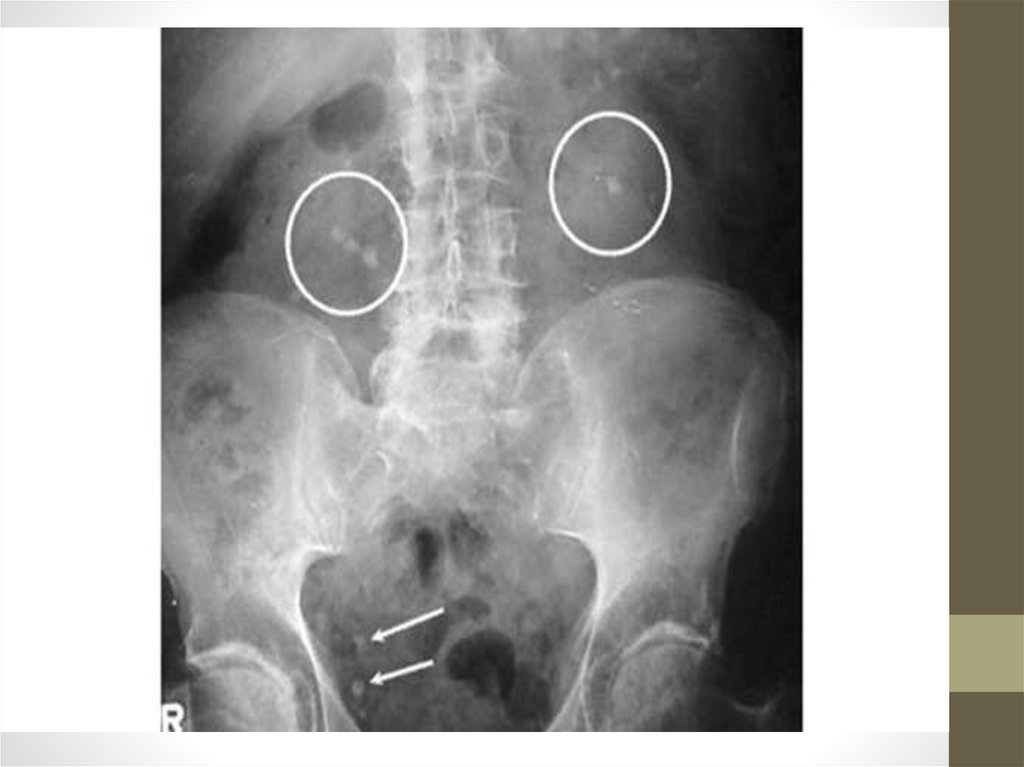

• При обследовании: (рентгенологическое, УЗИ)

выявляются камни, особенно хорошо выявляются

ураты, хуже - фосфаты.

• Рентгенологическое исследование, компьютерная

томография, радиоизотопное сканирование выявляют

тени конкрементов в почках.